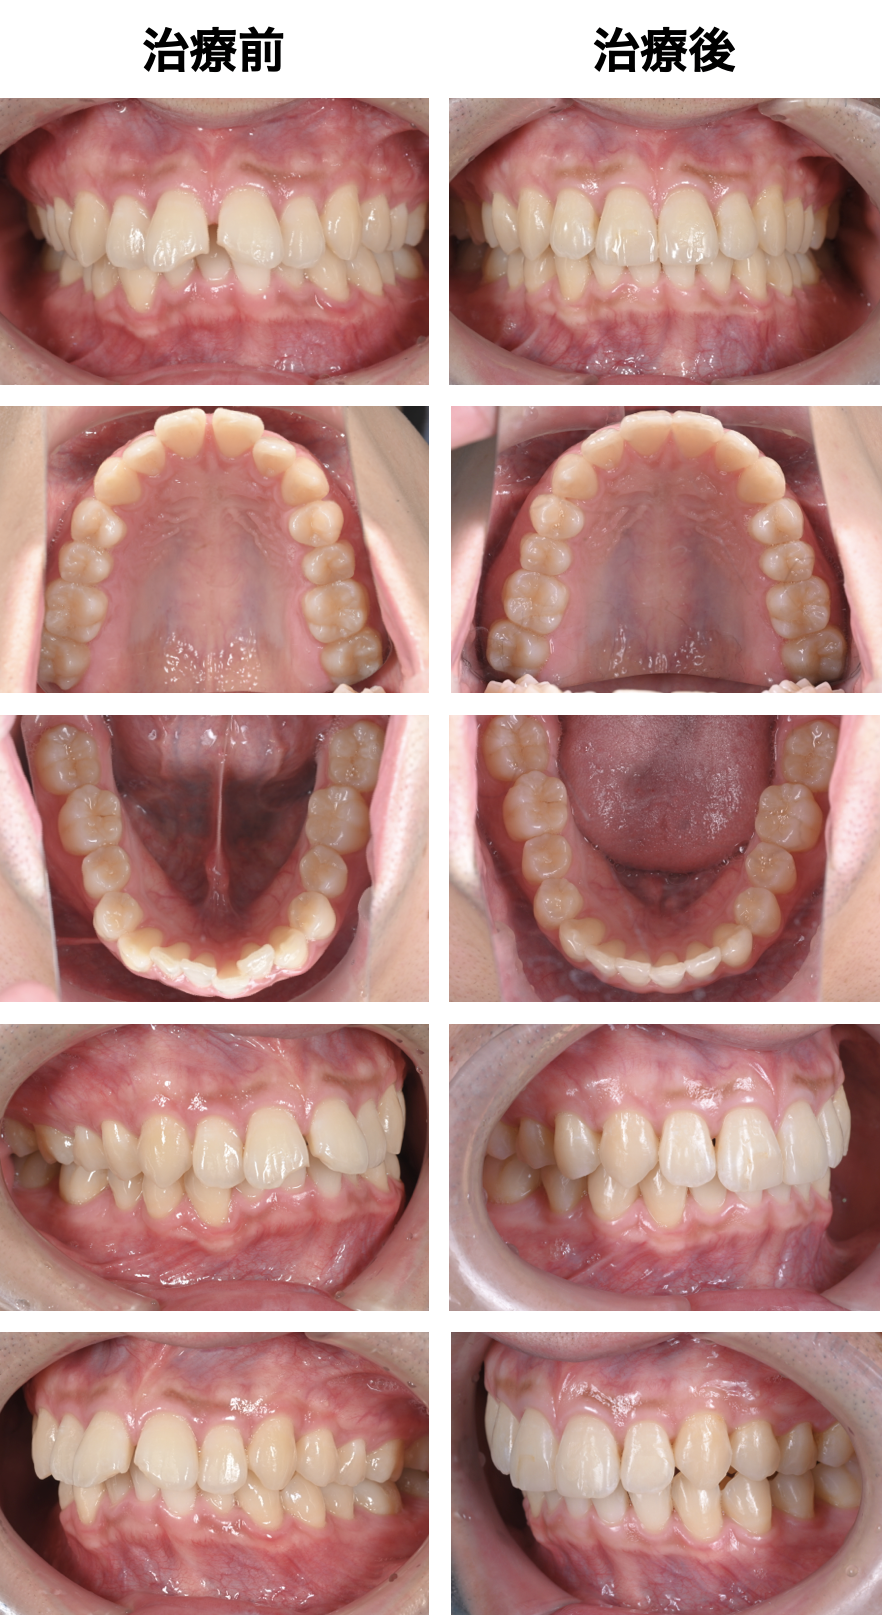

《治療の経過②》

矯正終了後に、再度打ダイレクトボンディングをやり直しました。

見た目に徹底的にこだわり、仕上げました。

《治療前後比較》